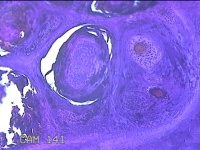

右侧中指皮下结节

性别

男

年龄

41岁

临床诊断

皮下结节

一般病史

发现右侧中指皮下结节3年余,无明显疼痛及不适。

标本名称

大体所见

灰白暗红色结节0.7x0.3x0.2cm一个,表面糜烂。